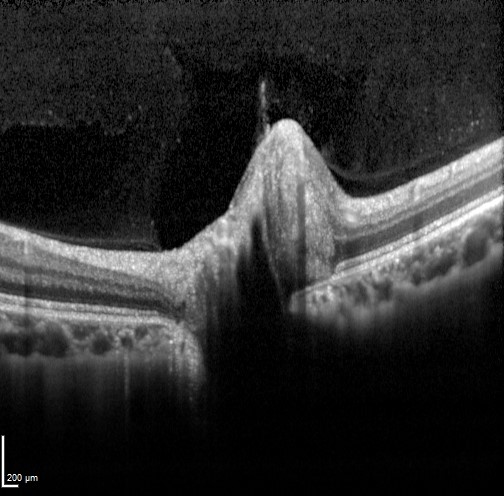

Clinical examination shows a smaller than normal disc with little to no visible cup. Fundus autofluorescence and B-scan ultrasound are unremarkable. OCT imaging shows an apparently elevated optic nerve with no apparent cup and a small Bruch's membrane opening. The retinal architecture adjacent to the optic disc is intact. The nerve may also show a "lumpy bumpy" appearance similar to that created by ONH drusen, however in a crowded disc this is actually due to posterior shadowing caused by the blood vessels trying to enter the small optic foramen. The hypo-reflective areas do not have the hyper-reflective borders seen in disc drusen (further information on disc drusen is available using the tab at the bottom of the page).

Spectralis OCT volume and line scan (right eye)

Spectralis OCT volume and line scan (left eye)